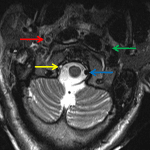

Indication: Trauma, CT showed fractures of the left occipital condyle, right C1 and C2 lateral masses, and right C3 transverse process

- Known fractures are not well demonstrated by MRI

- Extensive prevertebral soft tissue thickening and T2/STIR signal hyperintensity extending from the craniocervical junction to the level of C5

- T2/STIR signal hyperintensity in the C4-C5, C5-C6, and C6-C7 interspinous ligaments with overlying T2/STIR signal hyperintensity in the posterior paraspinal soft tissues at these levels

- Mild STIR signal hyperintensity in the supraodontoid space and right atlantooccipital joint

- Abnormal flow-related signal in the right internal carotid artery from the level of C3 through the skull base with circumferential mural T2 signal hyperintensity in the vessel most pronounced at the level of C1

- Abnormal flow-related signal in the right vertebral artery from the level of C1 through the distal V4 segment with areas of circumferential mural T2 signal hyperintensity more proximally in the vessel, most pronounced at the level of C3

- T2/STIR signal hyperintensity in the right periauricular soft tissues

- T2/STIR signal hyperintensity in the right mastoid temporal bone

- Traumatic arterial injury

Known fractures are not well demonstrated by MRI. No additional areas of marrow edema to suggest an additional fracture occult on CT.

Extensive prevertebral edema extending from the craniocervical junction to the level of C5 with evidence of interspinous ligament injury at C4-C5, C5-C6, and C6-C7. Mild edema in the supraodontoid space without disruption of the tectorial membrane or cruciate ligaments. Possible capsular injury involving the right atlantooccipital joint.

Abnormal flow-related signal in the right internal carotid artery from the level of C3 through the skull base and in the right vertebral artery from the level of C1 through the distal V4 segment concerning for traumatic dissection with slow flow versus occlusion. Circumferential mural T2 signal hyperintensity in both vessels raises concern for mural hematoma. Recommend CTA and/or catheter angiography for further assessment.